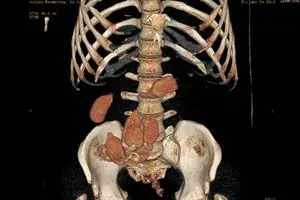

"En 2011 comenzaron a llegar personas que habían ingerido cápsulas líquidas. Éstas no son detectadas por placas, por lo que comenzamos a practicar tomografías computadas. El riesgo con la droga líquida es mayor porque, si bien es más fácil de ingerir, hay más posibilidades de que se perforen y esto puede ser letal para el paciente", explica la médica especialista.

El caso más impactante que les tocó fue el de un hombre que había ingerido 298 cápsulas. "Fue terrible porque fue difícil diagnosticarlo. Cuando nos dijo que eran más de 200 fue un shock. Pero lo más difícil fue darlo de alta, porque después de tantas evacuaciones y comidas no podíamos distinguir qué había en su organismo con una placa normal. Ahí comenzamos a usar la tomografía computada", relata Sorrentino.